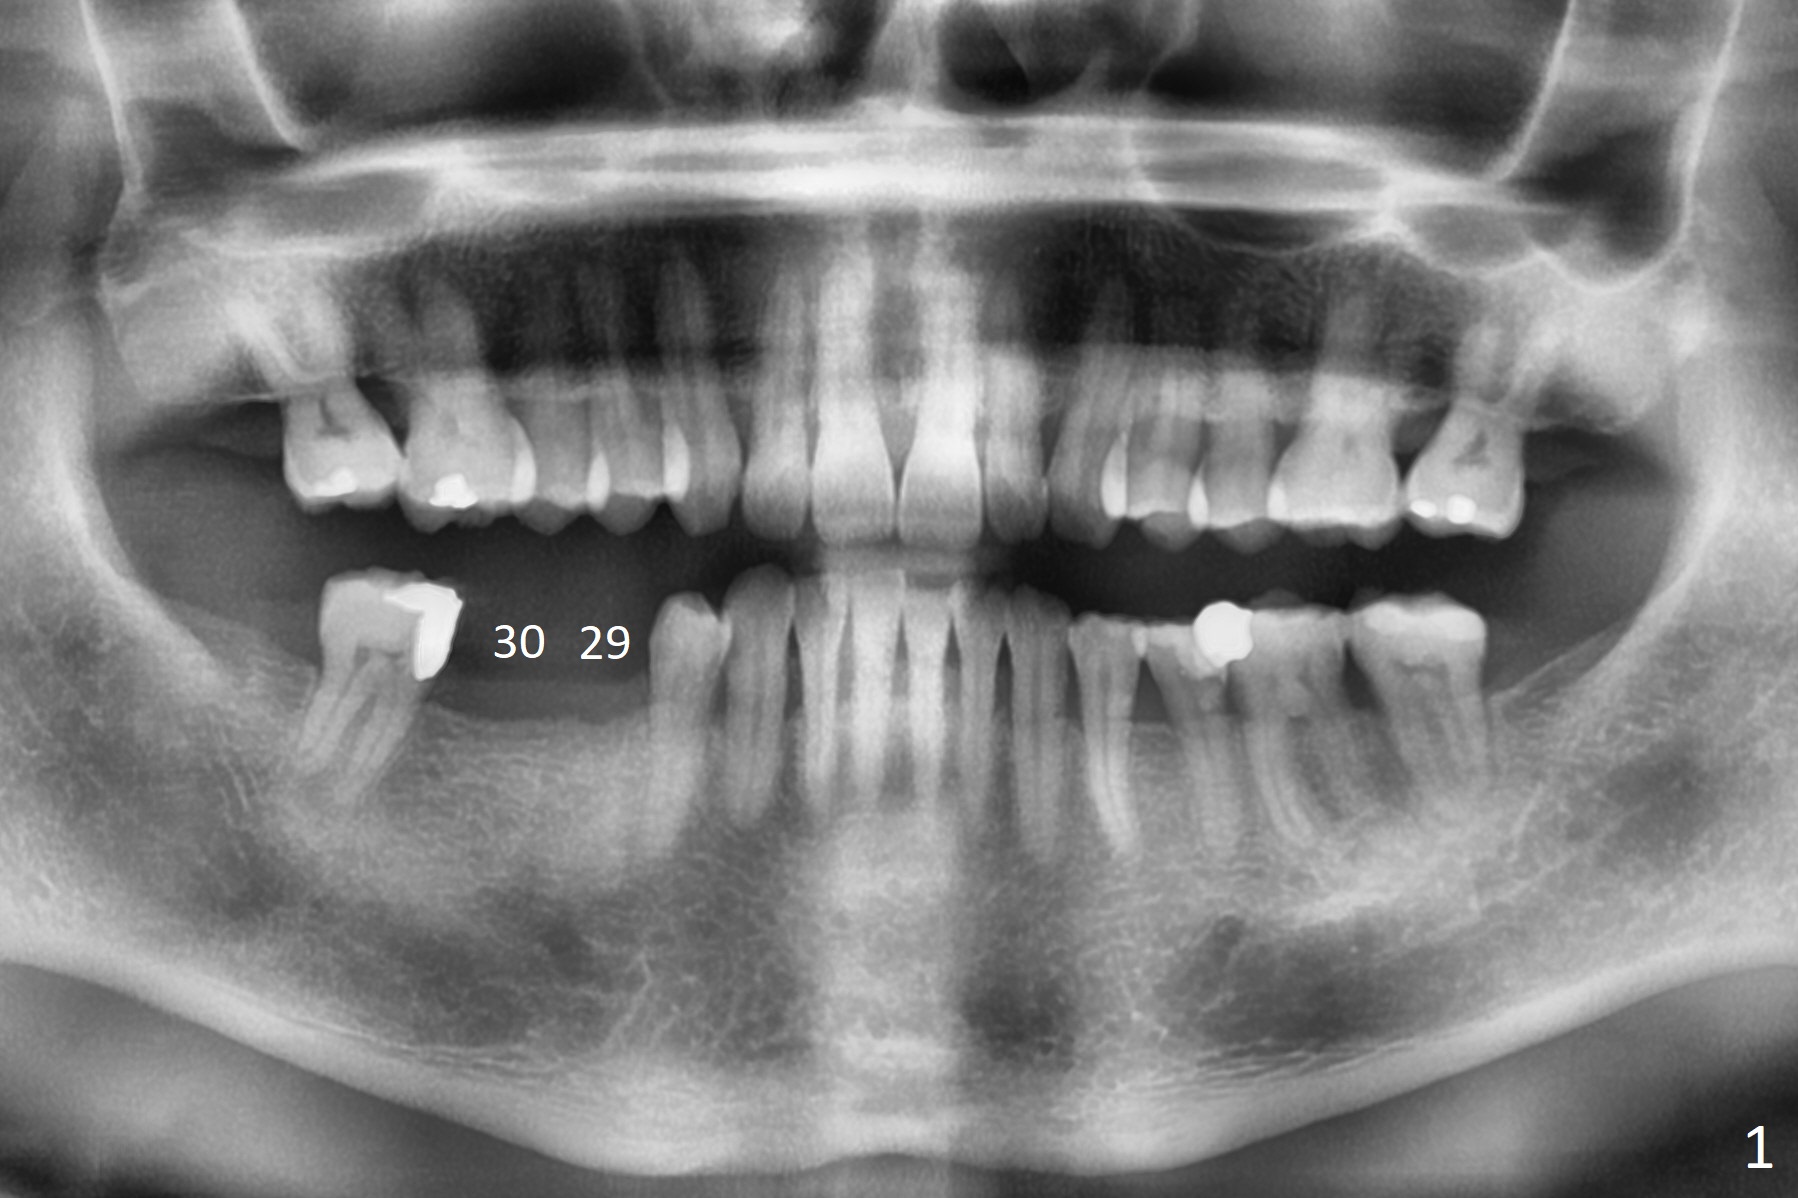

2 mm Bone

A 63-year-old man requests implants to replace a flipper at #29 and 30 (Fig.1). If torque is >25 Ncm for each implant (Fig.2,3 (2 mm bone buccolingually)), abutments will be placed immediately (using planning kit) for splinted provisional. Take photos for the flipper for a good bye party. Composite will be placed at #31 for MO leakage. Remove a small piece of residual root distal to #30 implant with curettage after osteotomy (Fig.4 <).